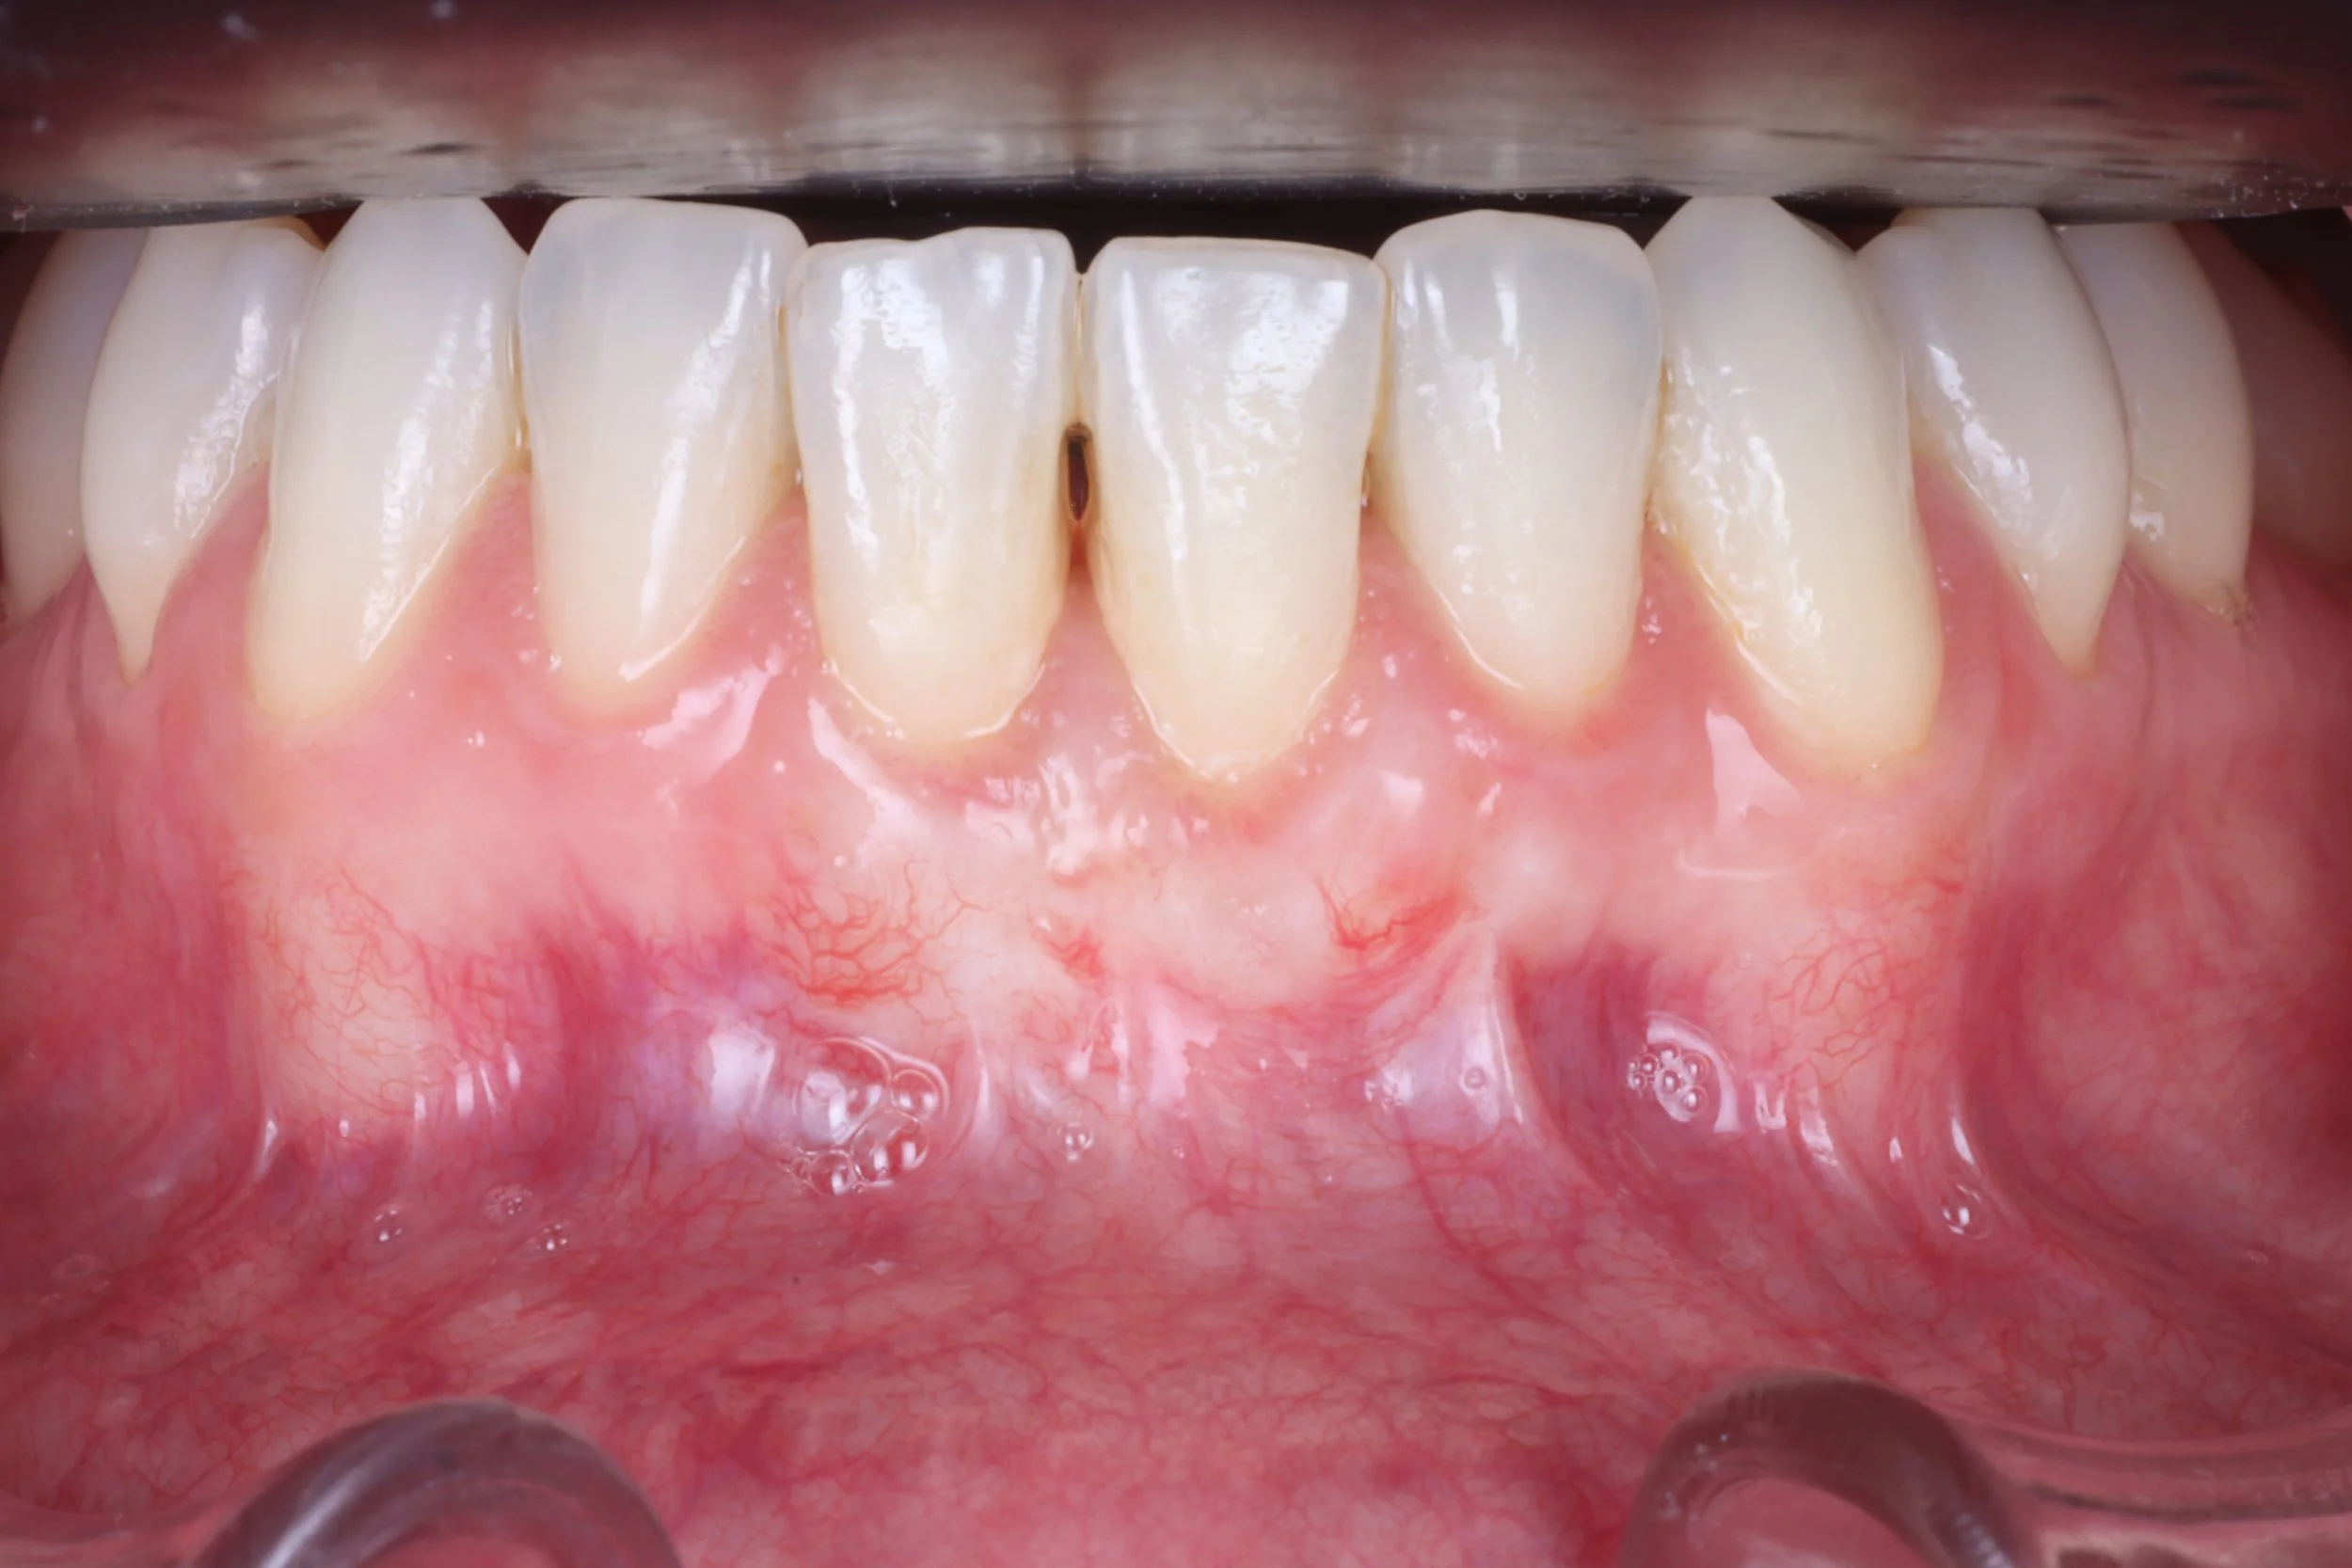

A nuestra clínica acuden pacientes con problemas de encías de sangrado, inflamación, sensibilidad, o retracción de encías que son tratados de forma individual, enseñándoles además como mantener las encías y mejorarlas, estableciendo un programa de citas de mantenimiento periódico.

• Injerto de encía